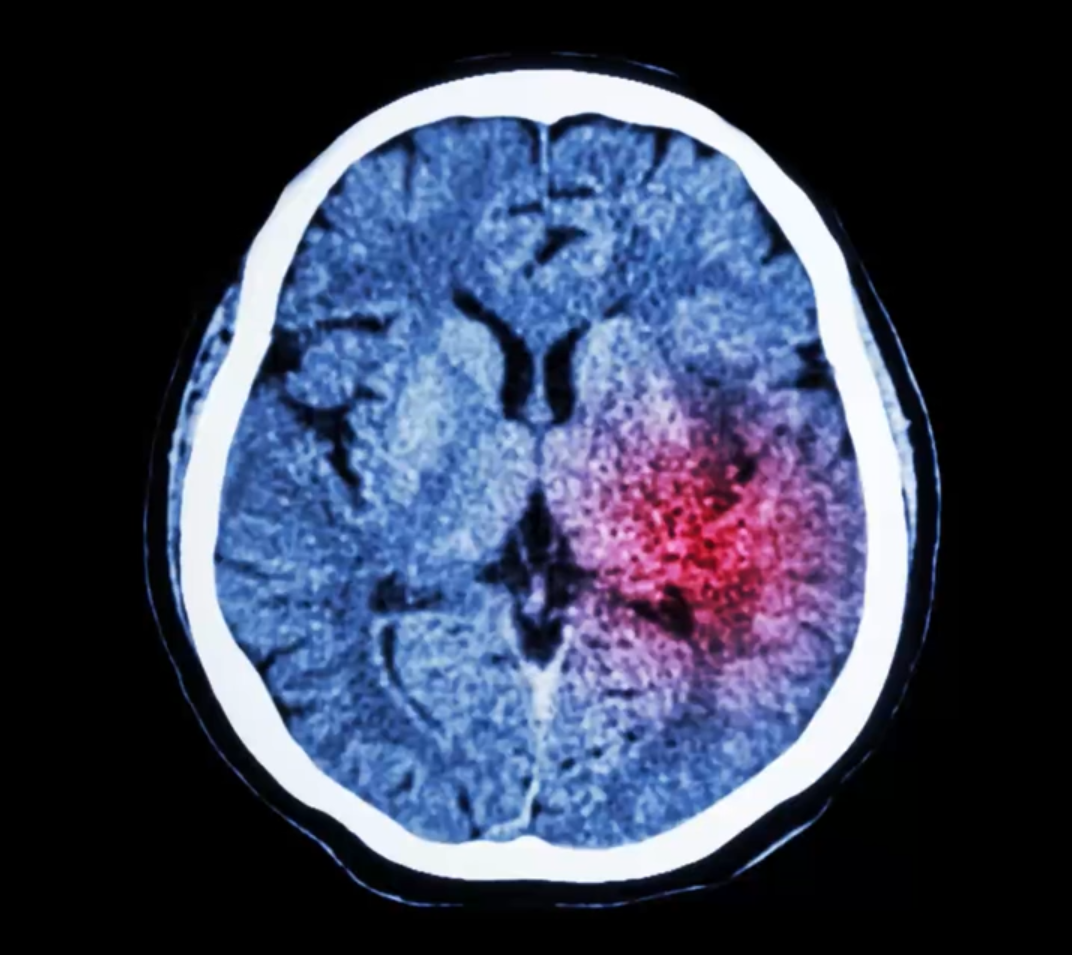

Hypoesthésie : l'AVC, une urgence qui nécessite une réaction rapide

L'accident vasculaire cérébral (AVC) survient lorsque la circulation sanguine vers ou dans le cerveau est interrompue par un vaisseau sanguin bouché (AVC ischémique, le plus fréquent avec 80 % des cas) ou par un vaisseau sanguin rompu (AVC hémorragique, environ 20 % des cas).

Chaque année, 150 000 Français subissent un accident vasculaire cérébral (on parle aussi d' " attaque "). " L'AVC se caractérise par une perte de sensibilité brutale qui atteint le plus souvent le bras et le visage du même côté, ou le bras et la jambe du même côté (on ne les " sent plus " du côté gauche ou du côté droit), explique le Dr. Thierry Anani. Cette perte de sensibilité dure plus de 5 minutes. "